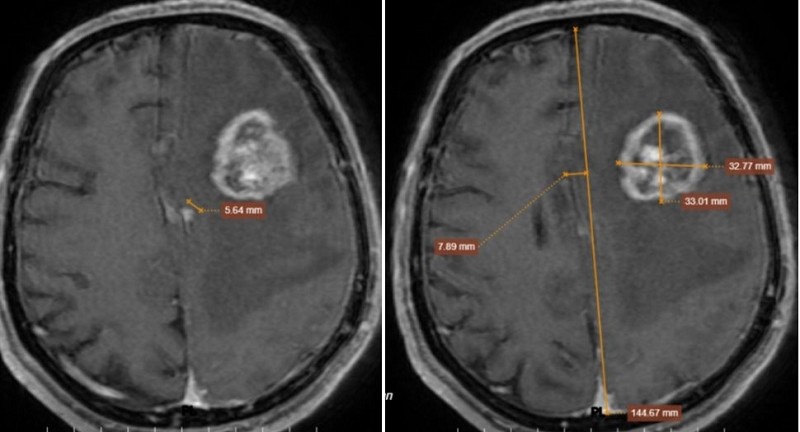

MRI phát hiện một khối choán chỗ tại vùng thái dương đỉnh trái, kích thước khoảng 32 mm, đồng thời xuất hiện nhiều tổn thương rải rác ở cả hai bán cầu và màng não. Phù não lan rộng gây chèn ép và đẩy lệch đường giữa gần 8 mm, dấu hiệu nguy hiểm có thể đe dọa tính mạng.

Trong trường hợp này, các tổn thương não xuất hiện nhiều ổ, phù não lan rộng và hình ảnh ngấm thuốc rõ, phù hợp với u não thứ phát, tức là di căn từ cơ quan khác.